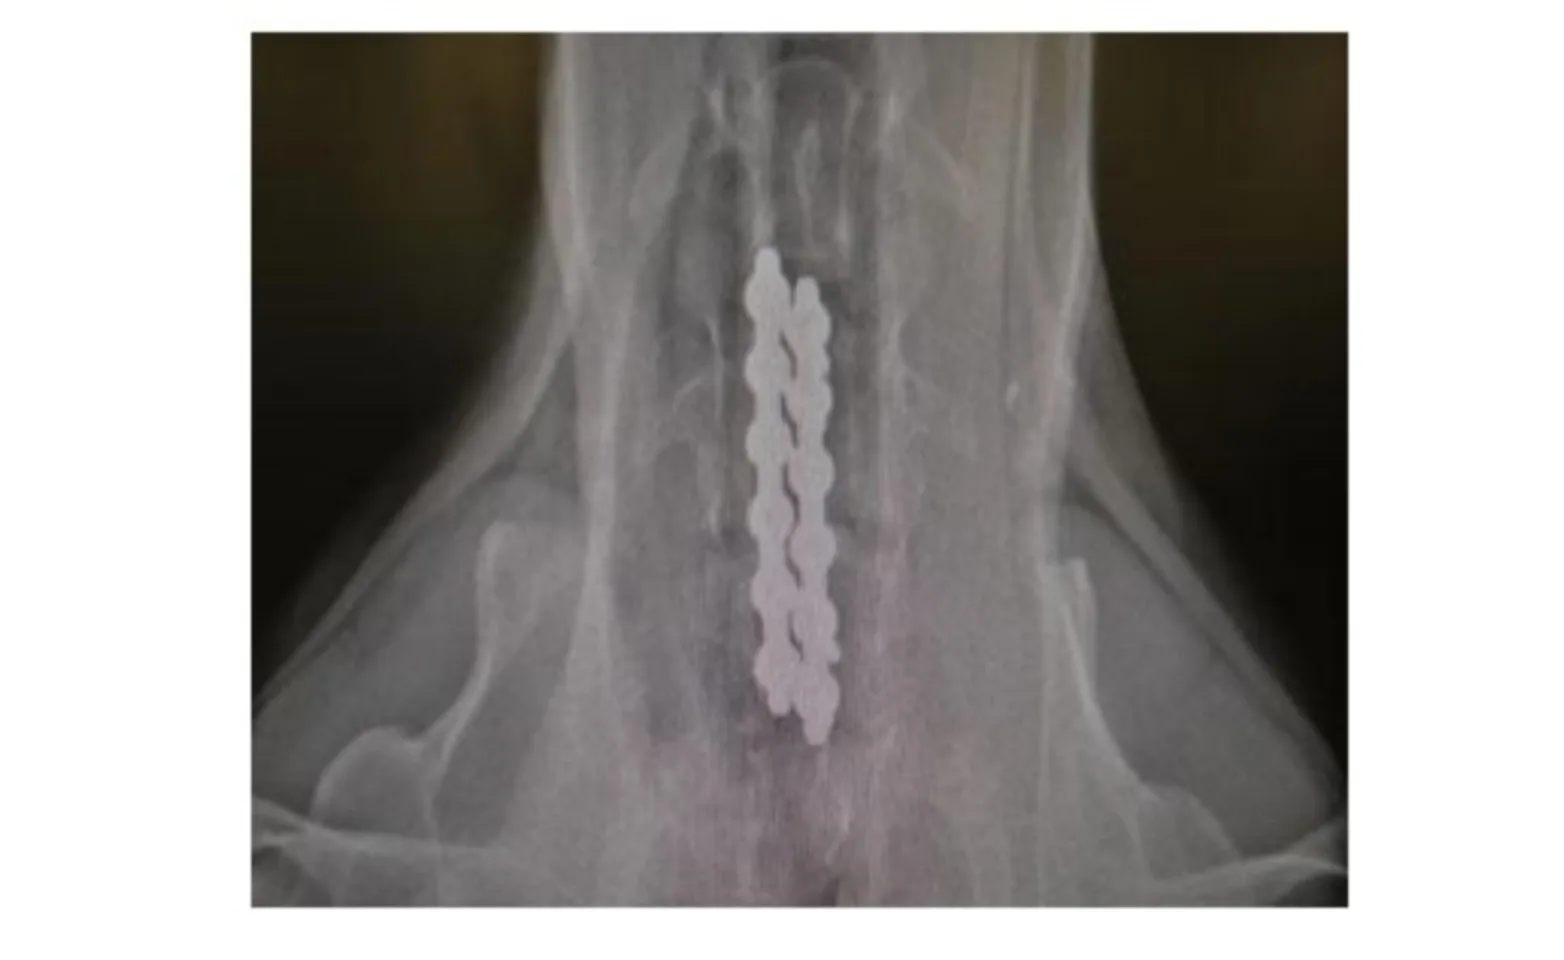

Surgical stabilization is the treatment of choice for the instability form of wobblers and generally carries a good to excellent prognosis. A partial ventral slot is performed in the central aspect of the two involved vertebrae and filled with cancellous bone. Intraoperative fluoroscopy is used to place 4 to 6 bone screws into the vertebral bodies. The screw heads are left protruding 1 - 1.5 cm ventral to the vertebra. Traction is applied across the affected vertebra resulting in flattening of the dorsal longitudinal ligament thereby relieving spinal cord compression. PMMA (bone cement) is placed so that it spans the two vertebrae and screw heads (Figure 2). This maintains the vertebrae in distracted position. The cancellous bone graft in the slot eventually causes the two vertebral bodies to fuse.